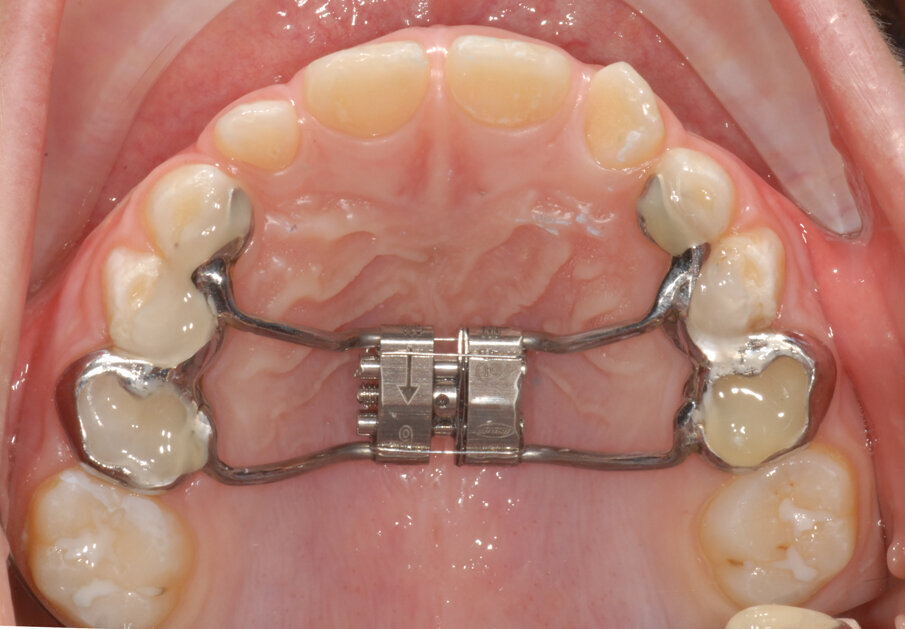

La piccola Sofia viene sottoposta a una prima visita ortodontica all’età di 8 anni, l’esame obiettivo (Figg. 1, 2) e l’ortopantomografia (Fig. 3) delle arcate dentarie evidenziano una mancanza di spazio per la corretta eruzione dei canini superiori (1.3-2.3).

Dopo aver rilevato delle impronte con polivinilsilossano per realizzare un espansore del palato, si esegue l’espansione rapida del mascellare (Figg. 5, 6) superiore con il dispositivo cementato sui secondi molari decidui (5.5-6.5). Al termine dell’espansione, sono rilevate delle nuove impronte con polivinilsilossano per realizzare una barra palatale (Fig. 6) ancorata sui primi molari permanenti (1.6-2.6); viene eseguito un protocollo di estrazioni anticipate dei primi molari decidui e dei canini decidui (Figg. 7-9).

Fig. 2_Vista occlusale iniziale.

Fig. 5_Espansore rapido del palato ancorato su “E”.

Fig. 6_Termine dell’espansione.